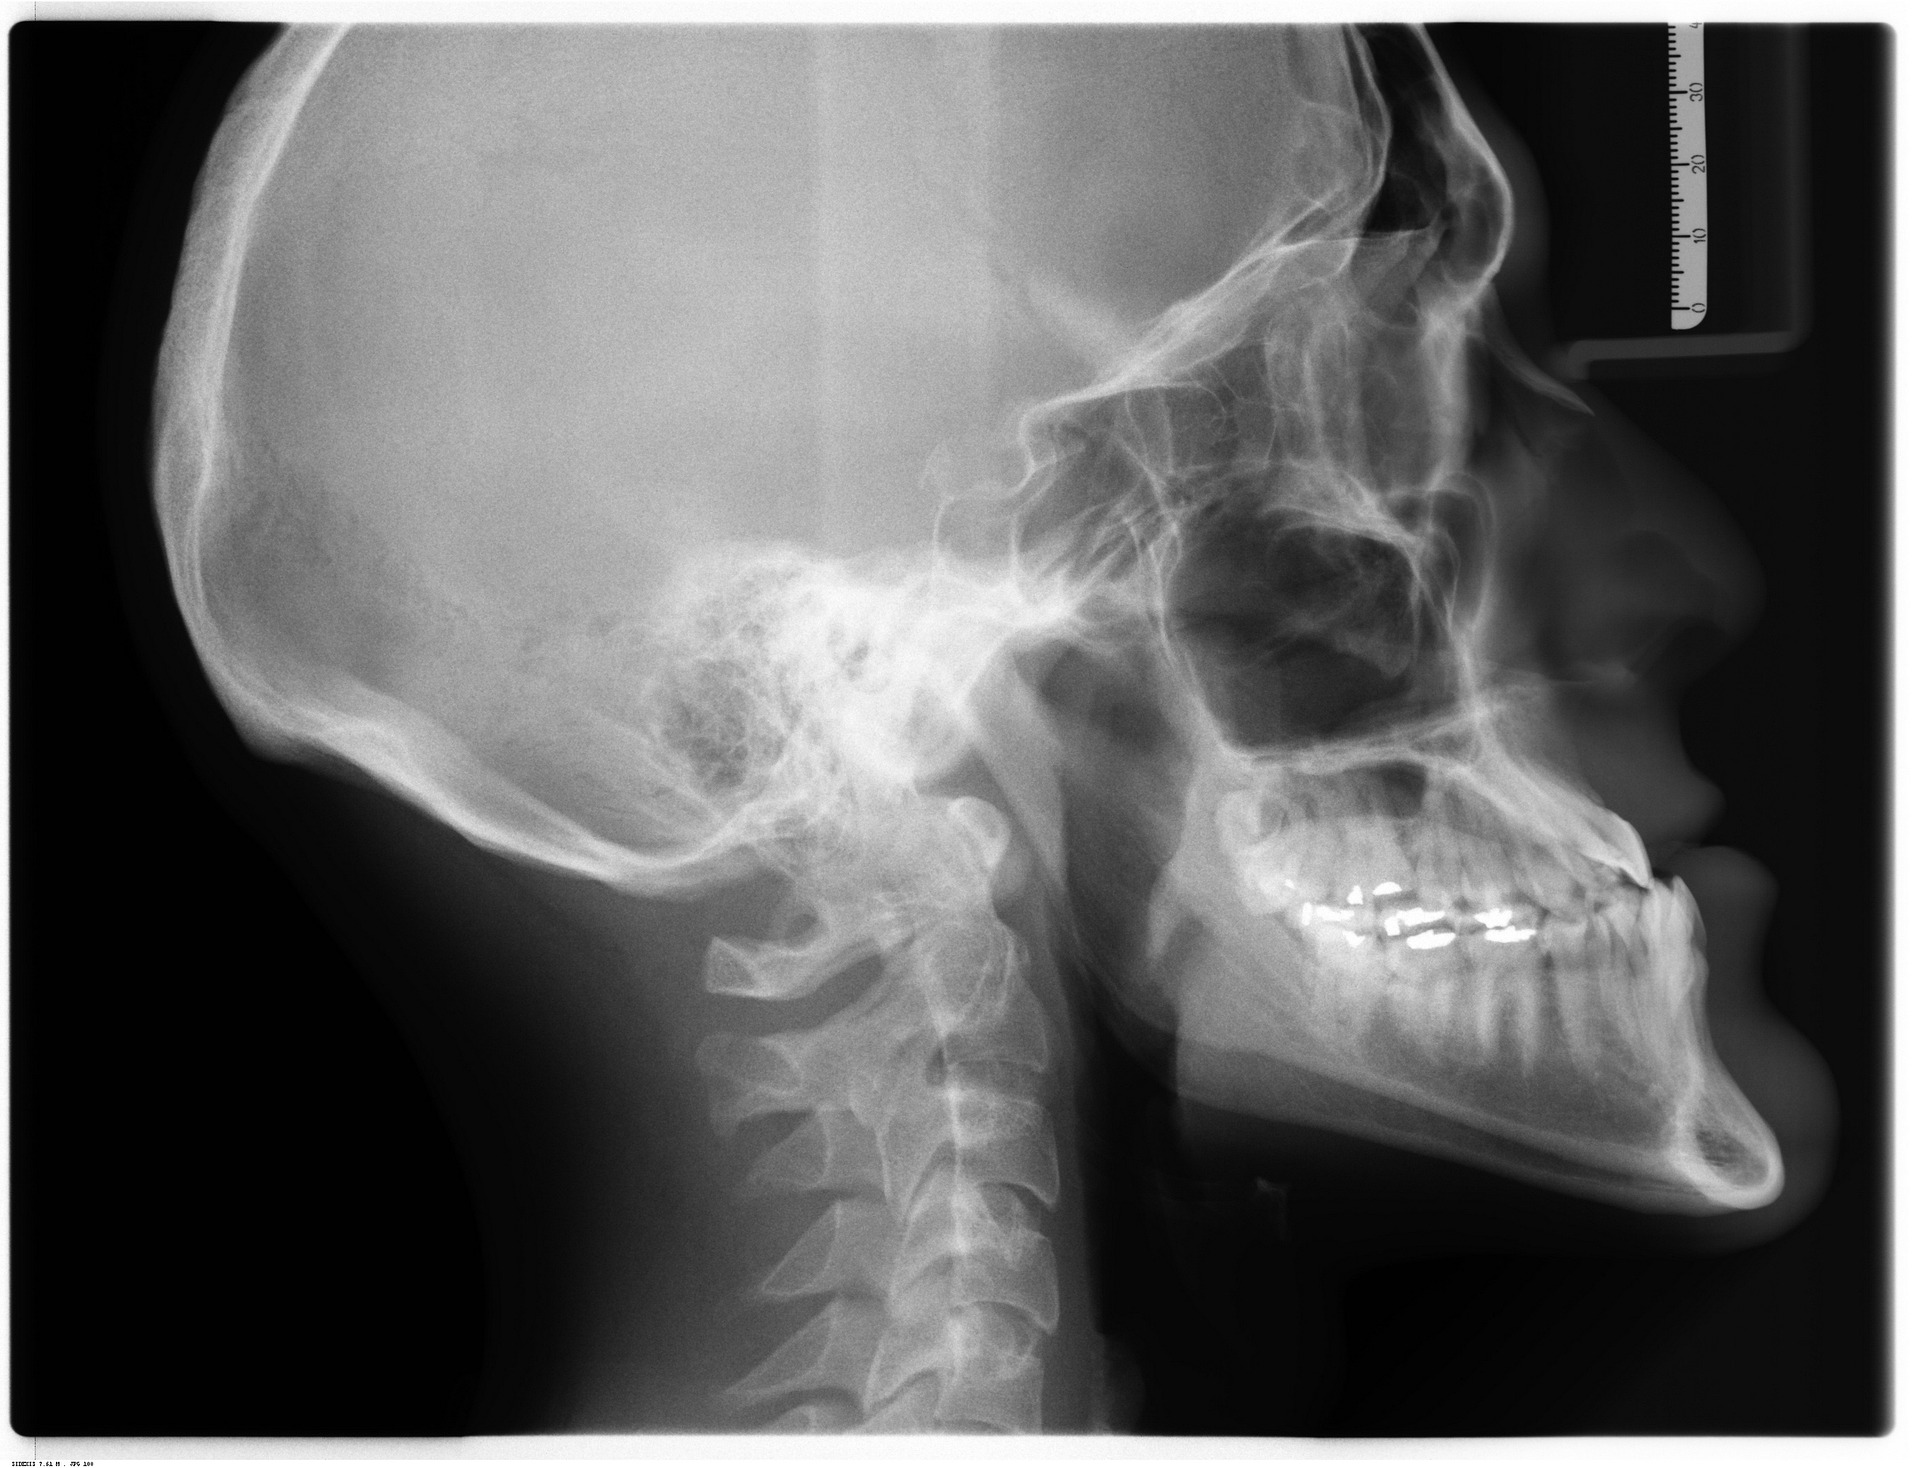

Radiology